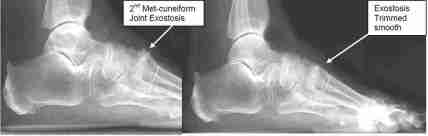

REMOVAL OF METATARSOCUNEIFORM JOINT EXOSTOSIS

Before and after photos